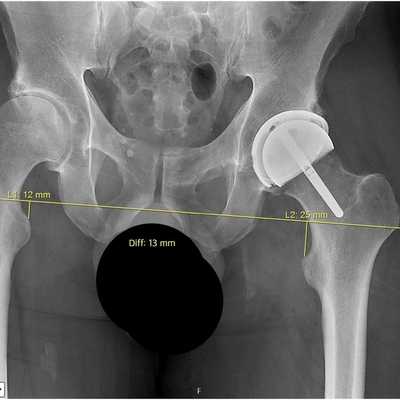

Click on an image below to view more info.